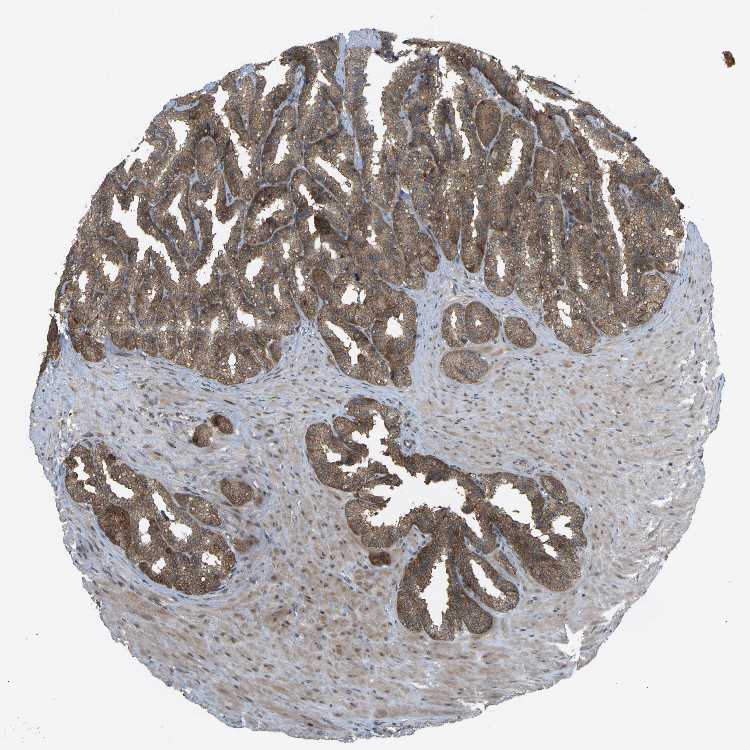

SEMINAL VESICLE